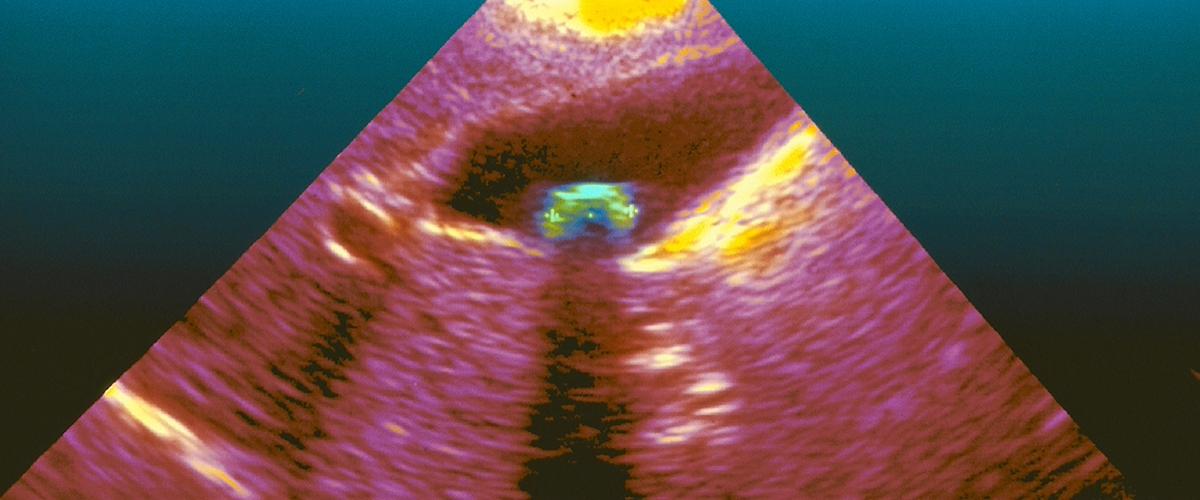

Созданный специалистами Университета Квинсленда кремниевый чип работает на эффекте фотоакустического ультразвука, когда лазер или иная технология генерирует акустический импульс в теле, а затем использует сенсоры для обнаружения акустической волны, проходящей сквозь него. Технология преобразит УЗИ: установка работает на частоте 1 МГц с чувствительностью, на порядок превосходящей все, чего удавалось достичь ранее, сообщает ZDNet.